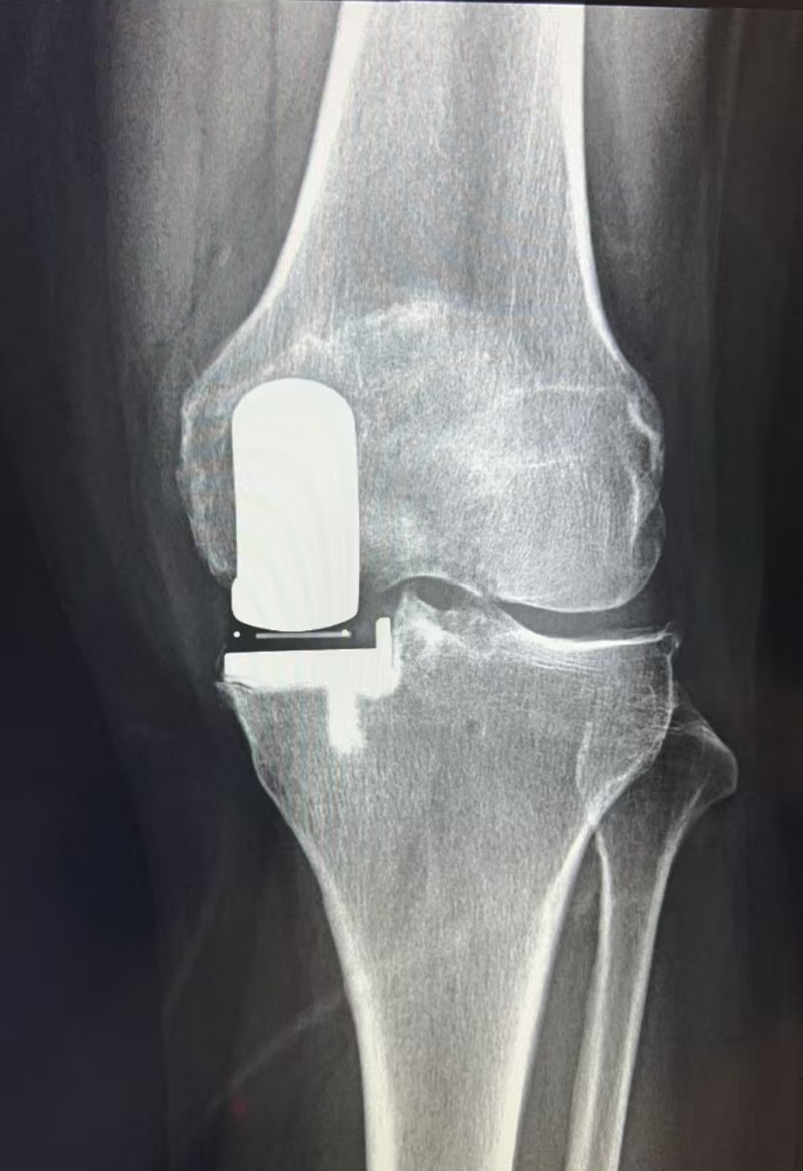

经过仔细评估,王歆峰主任决定给王阿婆做「左膝内侧单髁表面置换术」!这就是保膝治疗的一种,简单说,就是只修复膝盖磨损的那一部分,不用把整个膝盖关节换掉。手术很顺利。

保膝治疗,就像是给磨损的膝盖「修修补补」,而不是「全盘替换」。它针对的是膝盖局部磨损的部位,保留膝盖其他健康的组织和功能。

像王阿婆这样的中老年人,膝盖疼反反复复,确诊为膝关节骨性关节炎,而且磨损主要集中在膝盖的一侧,没有严重的畸形,大多都适合保膝治疗。当然,具体能不能做,还得医生经过详细检查和评估后才能确定。